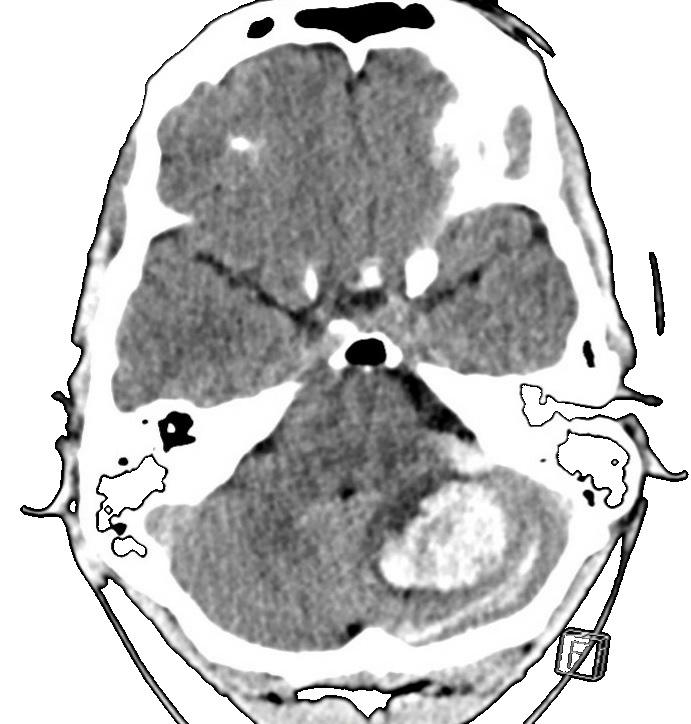

Yngre mand, der er tidligere rask. Han får pludselig indsættende hovedpine og herefter oplever han gradvist indsættende snurrende fornemmelse i ve. hånd. Derefter kvalme, svimmelhed og opkastning. Stadig svær hovedpine. CT af cerebrum viser cerebellar blødning. Påvirkning af 4. ventrikel. CT venøs angio viser sinus trombose.

Hvad vælger du som blodfortyndende behandling?

① Ingen behandling. Jeg vil ikke risikere forværring af blødningen.

② Fuld AK-behandling med 200IE Fragmin per kg. Sinustrombose skal behandles med AK på trods af blødning.

③ (Ufraktioneret) heparin drop. Måler APTT. Giver 5000IE som bolus, efterfulgt af drop og indstiller droppet efter 2-3 gange forlængelse af APTT. I tilfælde af neurokirurgisk intervention kan vi slukke droppet.

④ Modificeret AK behandling, Fragmin 5000IE x2. Min afdeling er ikke vant til at styre et heparin drop.